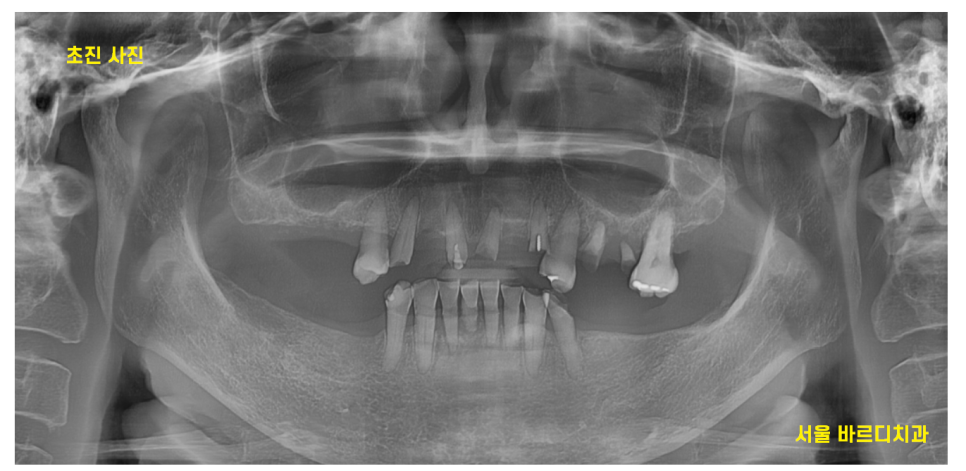

고덕역 치과를 내원하셨던 환자분입니다.

위아래 어금니가 전반적으로 빠진 상황에서

내원하셨는데요.

이렇게 치료할 치아가 많은 환자분들의 경우

최적의 치료 방법을 찾기 위하여

복기합니다.

입안 사진 촬영한 것으로도

확인할 수 있지만